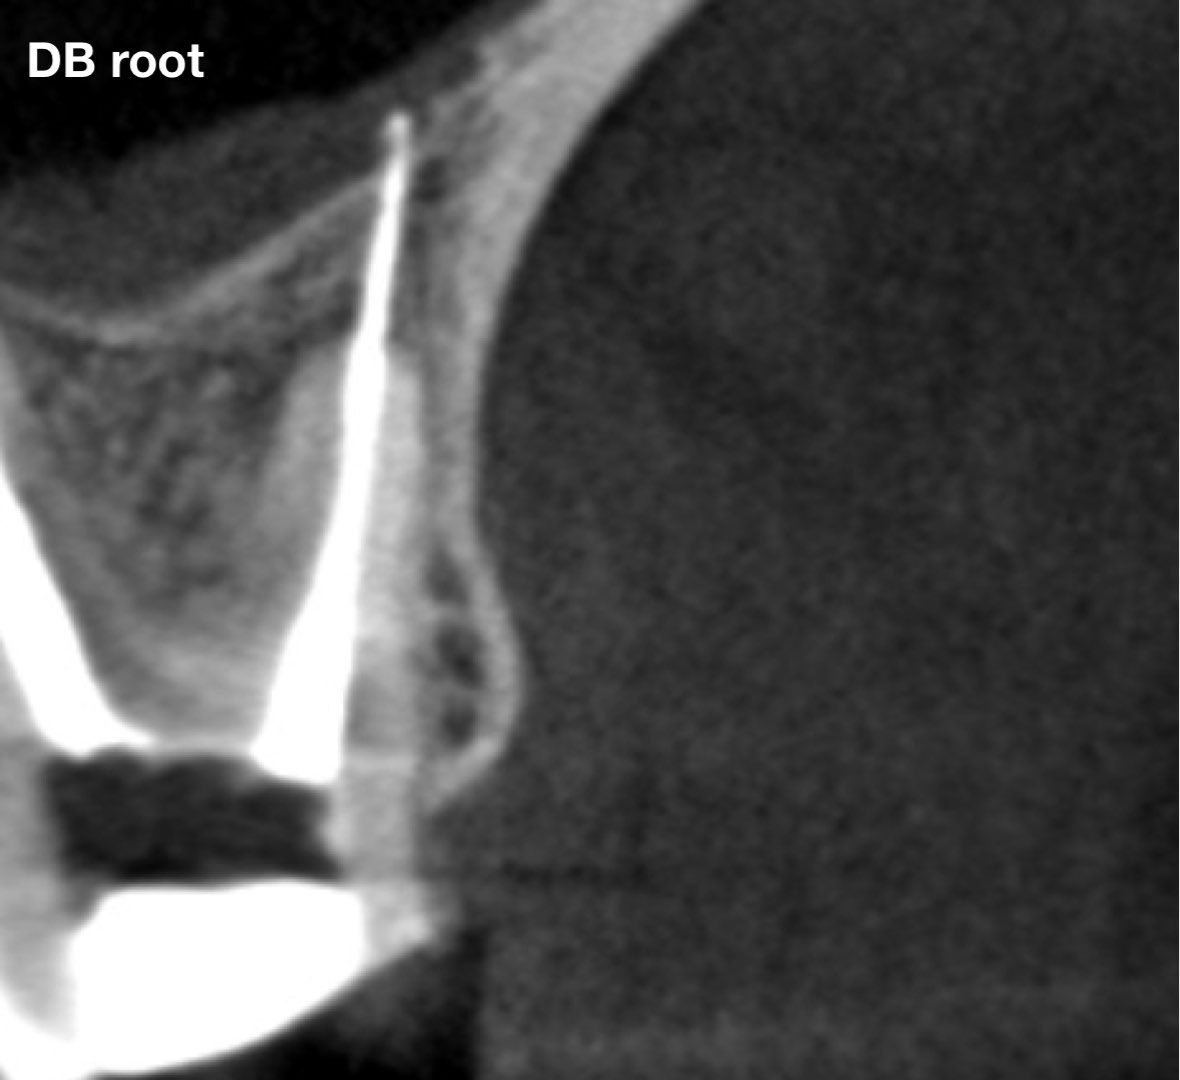

طبيب مقيم في علاج الجذور و عصب الأسنان 🦷 🦷 Endodontic resident at @ksmcmedia 📍Riyadh